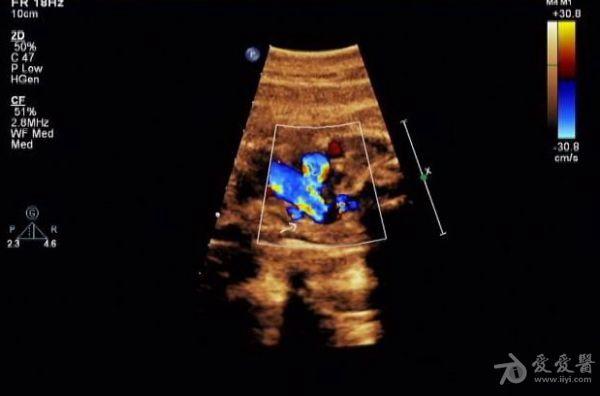

胎儿永存上腔静脉

冠状静脉窦增宽约

0.8 cm

,心底部三血管切面显示肺动脉左侧管腔样结构,频谱显示为静脉频谱。